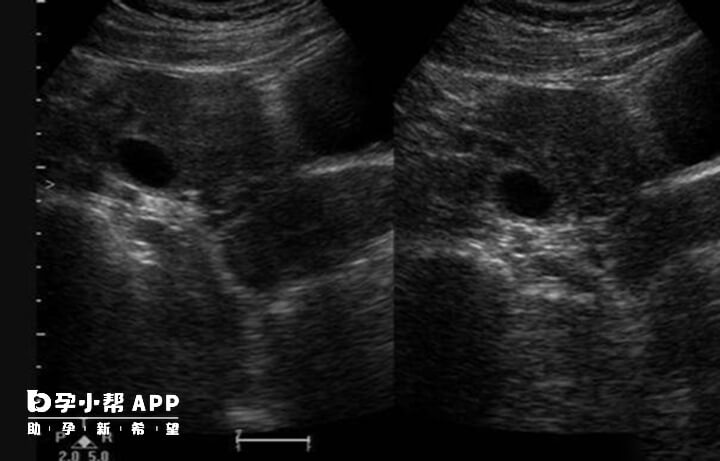

如果備孕期女性平時月經非常規律,通過超聲監測排卵的第一次檢查往往在月經週期第十天,從第十天開始做B超監測。醫生會根據卵泡發育大小,以及子宮內膜厚度的變化,告訴女性朋友間隔多長時間再來做。在經期後進行B超檢查,通常來說都是進行卵泡監測,但是對於優勢卵泡檢查的具體時間來說,並不是每一個人都知道的,所以對於什麼時候檢查卵泡最好,醫生建議B超在經期後的11天就可以進行了,這個時候的優勢卵泡大小都能夠看得出了,算得上是最佳的檢查時期。

其實即便卵泡監測能夠時時刻刻觀察都優勢卵泡的變化,但是在日常生活中使用的也並多,反而在試管嬰兒卵泡數量的使用中較多,而通常來說B超檢查優勢卵泡的最佳時間通常定在月經後的11天,方便做優勢卵泡多久排出推測,在最佳的時間進行同房也是能夠增加成功率的。

而對於B超檢查優勢卵泡通常來說,並不是對卵泡監測的,常常是針對卵泡的增長速度以有無排卵,對於觀察優勢卵泡可以長多大是一個非常不錯的方式,而對於B超檢查優勢卵泡來說也是分階段的。